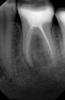

vovq Опубликовано 15 марта, 2011 Поделиться Опубликовано 15 марта, 2011 (изменено) Здравствуйте!Прокомментируте пожалуйста, хорошо ли запломбированы каналы, не нужно ли перелечивать? Собираюсь ставить коронки. Достаточно ли этих снимков, чтобы определить качество лечения? Изменено 15 марта, 2011 пользователем vovq Ссылка на комментарий

VIM Опубликовано 15 марта, 2011 Поделиться Опубликовано 15 марта, 2011 Здравствуйте!Прокомментируте пожалуйста, хорошо ли запломбированы каналы, не нужно ли перелечивать? Собираюсь ставить коронки. Достаточно ли этих снимков, чтобы определить качество лечения? Обязательно перелечивать . Ссылка на комментарий

zybnaya feya Опубликовано 15 марта, 2011 Поделиться Опубликовано 15 марта, 2011 Обязательно перелечивать .+1 пеелечивать у доктора,который работает машинной эндодонтией Ссылка на комментарий